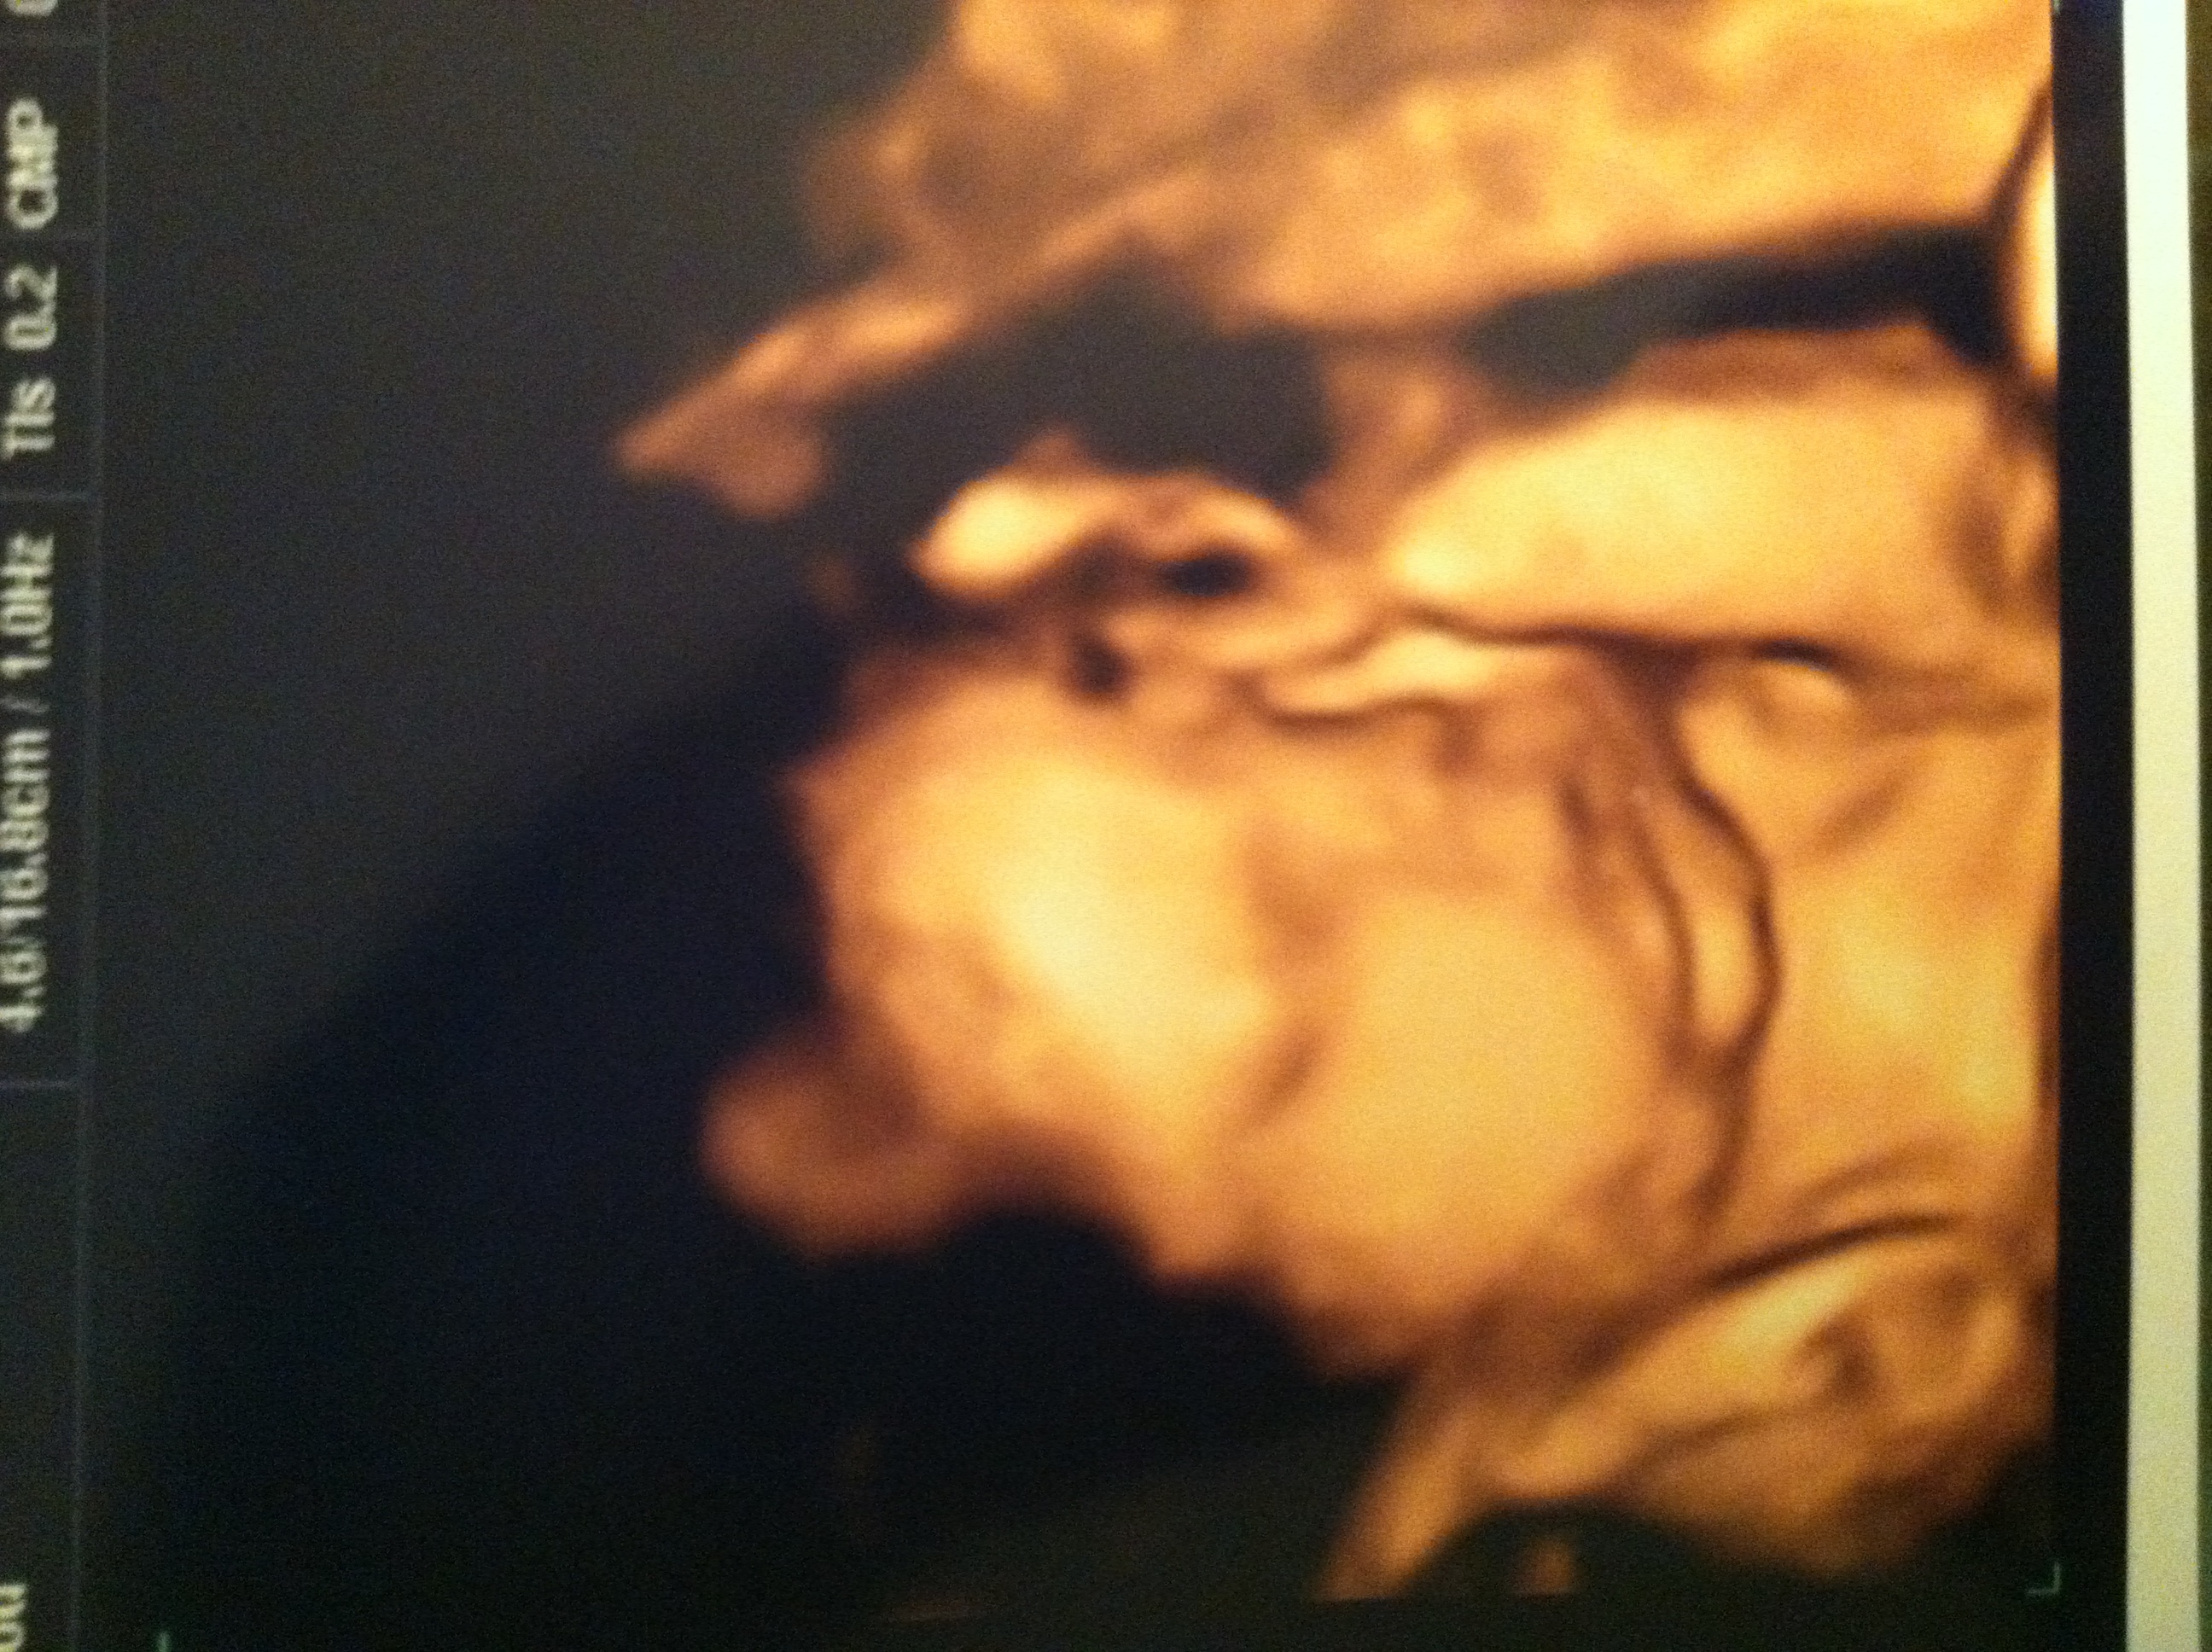

Patiently waiting for little brother!